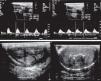

El paciente ingresó por presentar un cuadro de derrame pleural derecho el cual remitió tras el tratamiento médico; se solicitó valoración por el servicio de urología debido a lesión ulcerada en la cara dorsal del glande de 3×2cm con bordes eritematosos con secreción fibrinoide amarillenta (fig. 1). Presentaba dolor intenso, tratado con ciprofloxacino parenteral y analgesia; el paciente no presenta antecedente de contacto sexual de alto riesgo ni lesiones traumáticas locales. Sus análisis de laboratorio de ingreso muestran hemoglobina de 13.2g/dl; hematocrito 39.8%; plaquetas 147,000; leucocitos 8.6; neutrófilos 68%; linfocitos 24%; glucosa 523mg/dl; BUN 23.9; creatinina 4.86; sodio 131; potasio 4.1; cloro 92; calcio 8.8; fósforo 4.4; magnesio 2.5; tiempo de protrombina 91.5; INR 1.10; fosfatasa alcalina 190; proteínas totales 6.8g/dl; albumina 2.49g/dl; y deshidrogenasa láctica 118 Se obtuvo cultivo positivo para Escherichia coli sensible a ertapenem; se ajusta el tratamiento antibiótico sin presentar disminución en el tamaño de la úlcera o mejoría, incrementando el dolor. Se realizó ultrasonido doppler de pene y uretral (fig. 2a) en el que se observa arteria cavernosa derecha e izquierda, ambas con un diámetro de 0.08mm; con la aplicación de vasoactivo se observó respuesta parcial; las arterias cavernosas no incrementaron su diámetro, en ambas arterias se obtuvieron picos sistólicos con velocidades menores de 25cm/s y diastólicos disminuidos, y en la porción distal del pene se observan imágenes cálcicas difusas (fig. 2b). Se concluyen datos de insuficiencia arteriogénica moderada. Ingresó a quirófano en donde se realiza biopsia transoperatoria de la lesión ulcerada, reportándose úlcera con presencia de tejido de granulación que involucra la superficie del espécimen, depósitos de calcio en la media, íntima y en la luz en el 40% de los vasos arteriales, con oclusión vascular que varía del 20-100% (calcifilaxis), fibrosis difusa del estroma y cambios secundarios a daño isquémico crónico (fig. 3).

El conocimiento de la vasculatura peniana, la confirmación de flujo arterial de las arterias cavernosas y flujo vascular uretral mediante ultrasonido doppler peniano previo a la decisión de realizar una cirugía de este tipo, nos dio fundamento para realizar esta cirugía. La vasculatura uretral y de la piel genital es fundamental en procedimientos reconstructivos. La uretra puede ser movilizada de manera extensa ya que cuenta con una irrigación arterial bidireccional, es decir, anterógrada y retrógrada (fig. 10). La arteria peniana común, rama de la pudenda interna, tiene 2 ramas iniciales que son las arterias bulbares y cavernosas circunflejas (que irrigan el cuerpo esponjoso proximal de manera anterógrada (fig. 11). La arteria dorsal del pene se ramifica de manera importante en el glande y se continúa hacia las arterias uretrales del cuerpo esponjoso de forma retrógrada. Estas se bifurcan en 2 arterias centrales cavernosas y en la arteria dorsal del pene. La arteria dorsal del pene se divide en múltiples ramas que van a penetrar el glande y posteriormente llevarán el flujo arterial sobre el esponjoso distal en forma retrógrada.